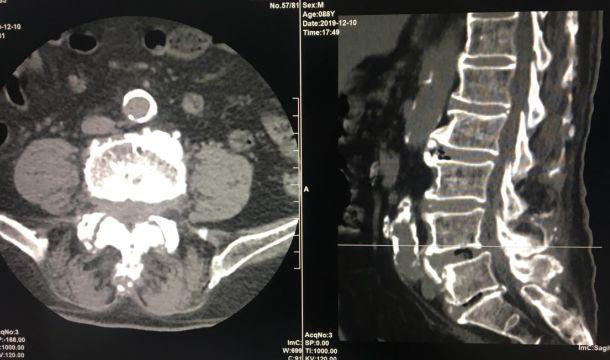

全新日本进口佳能金刚螺旋CT

该新设备功能先进,有平扫、三维重建、X线计算机体层成像等功能,能对人的头部、颈部、胸腔、四肢、盆腔等多个部位进行扫描成像。

放射科秦主任介绍到,该设备的引进和使用,意味着蒙自市中医医院放射科迈出了从无到有的关键性一步。

以前,咱们医院里是没有该设备的,患者到医院就诊时如果遇到需要做CT,就只能转到州、市第一人民医院去,这样无形中就耽误了患者确诊和治疗的时间。

现在医院引进了全新的进口螺旋CT,患者直接就能在医院确诊,节约了患者的时间,并且,进口的螺旋CT机扫描图像质量好,显示清晰。

该设备自运行以来,发现并确诊不少疾病:颈椎椎间盘突出、 腰椎椎间盘膨出伴双侧神经根受压、硬膜外血肿、右侧上颌窦炎、右侧筛窦炎、双肺感染伴双侧胸腔积液、心包积液、右侧胸腔包裹性积液、原发性肝癌伴骨转移等疾病。